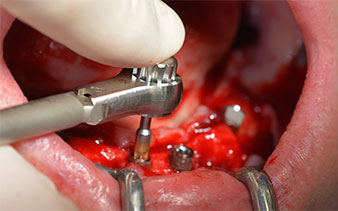

The next programmed setting is already for placement of the implants. In our practice we usually employ a torque of 32 Ncm to place the implants (Fig. 12 and 13).

W&H contra angle

Fig. 12

torque of 32 Ncm

Fig. 13

High primary stability is an absolute requirement for an immediate restoration. In order to achieve this, the hole was not tapped in this case. The W&H Implantmed drill unit used here is equipped with a suitable special mode for this, which can also be directly selected and is indispensable for many indications. The final revolutions when placing the implants exceeded the value of 32 Ncm and were performed by hand. In such cases, we recommend utilizing the implants’ self-tapping function and twisting the implants backwards and forwards several times. This allows the implant to approach the final position gradually without exerting excessive pressure on the bone (Fig. 14).

Implants

Fig. 14